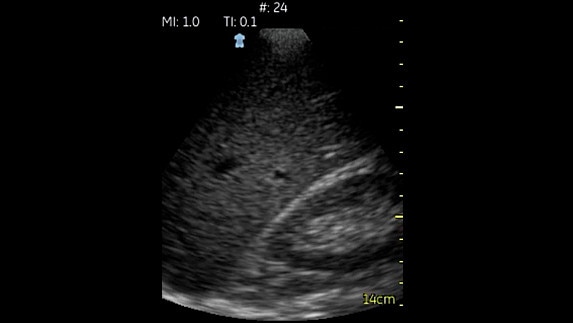

OB